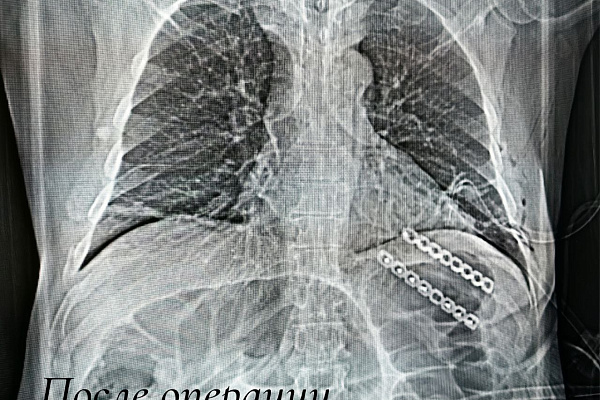

Сначала посредством малоинвазивного торакоскопического доступа выполнили пластику грыжи и вернули лёгочную ткань обратно в плевральную полость. Затем понадобился открытый доступ к месту перелома, чтобы устранить дефект рёбер. Их зафиксировали методом накостного остеосинтеза. Специальные пластины будут удерживать ребра в правильном положении, создавая условия для скорейшего сращения. Удалять конструкцию не потребуется. Восстановление пациента в раннем послеоперационном периоде прошло благополучно, сегодня он наблюдается амбулаторно.